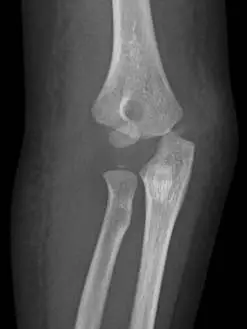

本題影像與上題相同,為治療前的診斷影像:

正面(AP)影像: 可見肱骨外髁骨折碎片明顯移位,位移超過 4 mm,骨折碎片(包含肱骨小頭骨化中心)向外側及遠端旋轉移位。依據 Jakob 分類為 Type III(移位 > 4 mm 且碎片旋轉),為高度不穩定骨折。